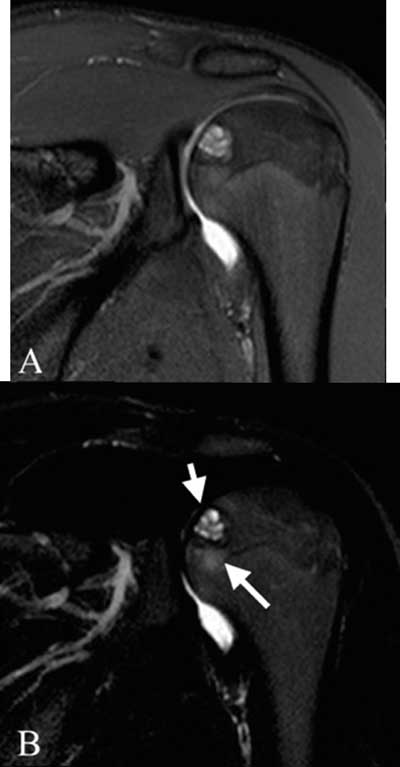

Figure 1

Coronal dual TSE FS images of the left shoulder. (A): proton density weighted image: well described lesion in the proximal humeral epiphysis without disruption of the subchondral bone plate, (B): T2-weighted: central high signal intensity (short arrow), limited bone marrow edema (long arrow).